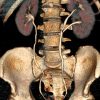

– Thận đôi (Duplex kidney): 2 đài bể thận riêng biệt thoát ra từ 1 thận.

– Đường bài xuất đôi (Duplex collecting system):

+ Niệu quản đôi (Double ureter): 2 đài bể thận với 2 niệu quản riêng biệt đổ vào bàng quang.

=> Hệ niệu đôi hoàn toàn: 2 đài bể thận và 2 niệu quản riêng biệt. Với hệ niệu đôi hoàn toàn, niệu quản dưới thường cắm vào bàng quang ở vị trí bình thường nhưng theo chiều vuông góc với thành bàng quang => làm cho niệu quản dưới hay bị trào ngược. Niệu quản trên cắm vào bàng quang ở vị trí thấp hơn và ở trong so với vị trí bình thường => đầu tận của niệu quản thường phồng lên trong lòng bàng quang tạo thành nang niệu quản với một miệng hẹp đổ vào lòng bàng quang